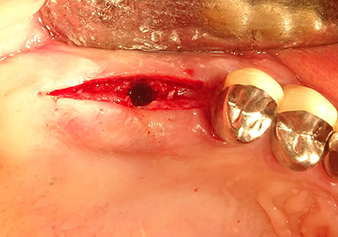

Following an intermediate check (Fig. 4) a further preparation step was performed (Fig. 5). Afterwards, the hydraulic Z35P instrument was used to lift the membrane to the desired position (Fig. 6 and 7). This was followed by further piezosurgical preparation of the implant bed, concluded with a rotary bur and shoulder milling cutter up to the implant diameter of 4.8 mm. Before the implant was inserted, the augmentation material (particle size approx. 0.8-1.6 mm) was introduced underneath the Schneiderian membrane (Fig. 8).